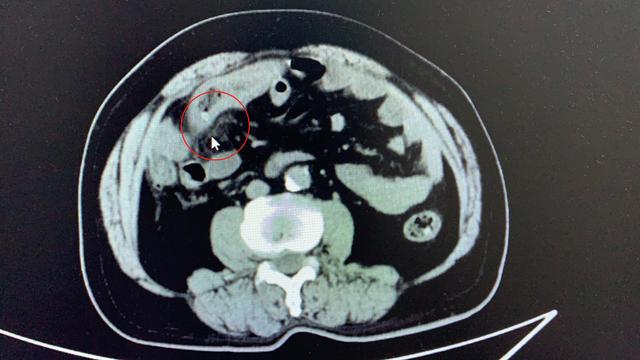

【红枣|一颗红枣下肚 老人痛失部分小肠】“医生 , 快给我看看 , 我肚子快疼死了” , 4日凌晨 , 在武汉市第四医院急诊科内 , 64岁的张先生捂着肚子向医生求助 。 2天前 , 张先生腹部开始隐隐作痛 , 刚开始张先生并未在意 , 随着时间流逝 , 疼痛越来越剧烈 。 凌晨1点多 , 痛的满头大汗的张先生被家人送到武汉市第四医院就诊 。 该院胃肠外科宋亚锋医生接诊后 , 详细询问了张先生病情 , 并为其进行相关检查 。 CT检查显示 , 张先生右中腹部医生发现张先生小肠管壁水肿增厚 , 其中还有一个高密度影 , 穿透了肠管管壁 。 张先生出现发烧症状 , 抽血检查也显示张先生白细胞高达2万多 , 远超正常值 。 种种迹象都表明张先生可能不小心吞下了异物 , 并刺穿了小肠 , 导致穿孔、炎症 。

难道张先生不小心把骨头茬吞到肚子里了?手术探查 , 医生发现张先生小肠上确实有两个明显的破洞 , 肠道内的粪便、消化液也漏到腹腔 , 导致了腹腔感染 。 进一步检查发现 , 刺穿张先生肠道的并非骨头 , 而是一枚两头尖尖的枣核 。 医生为其切除破洞处大约7-8厘米的肠道 , 并反复冲洗污染的腹腔 。 手术顺利完成 , 目前张先生已转危为安 。